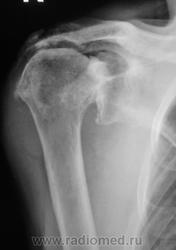

Двусторонний деформирующий остеоартроз: справа усилен верхним подвывихом с образованием неартроза с акромиальным отростком.

2-сторонний ДОА, справа подвывих, неоартроз + калькулезный (известковый) бурсит(возможно тоже 2-сторонний)

у одной из моих больных подобная R-картина-РА

В левом суставе - вероятно изменения за счёт артроза, обызвествления связок

В правом - последствия травмы (подвывих, перелом головки?)